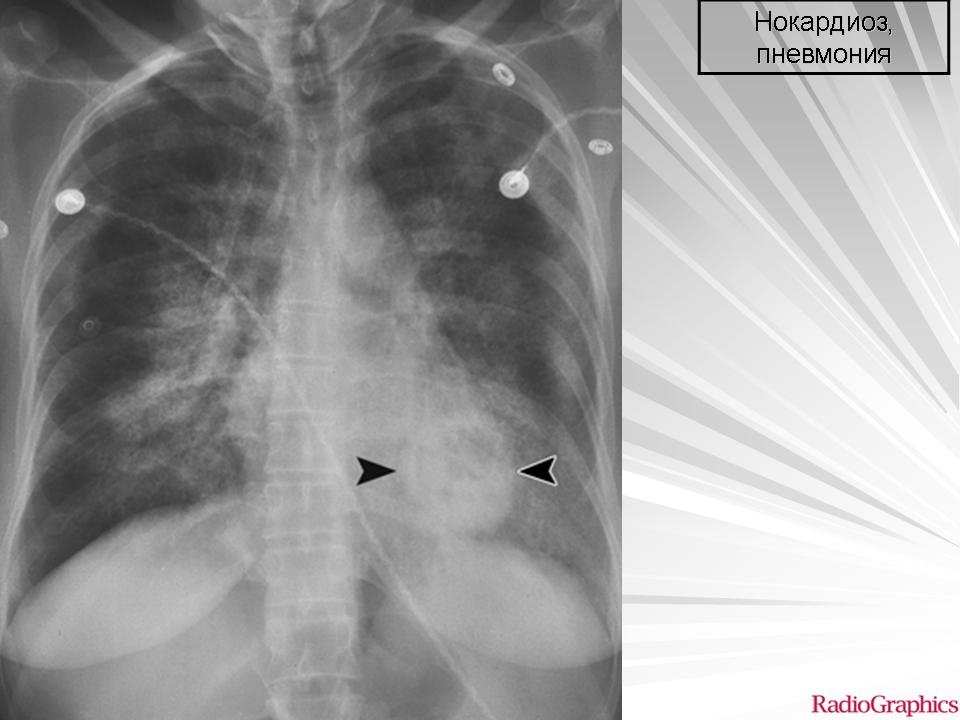

Легочная инфекция, вызываемая Nocardia, редкая, но серьезная, которая обнаруживается главным образом у пациентов с иммуносупрессией. Даже когда клиническое подозрение на нокардиоз велико, заболевание часто путают с другими нагноительными заболеваниями легких и опухолями.

Возбудитель вызывает острую, часто некротическую пневмонию, обычно ассоциированную с образованием полости. Другие проявления заболевания могут включать медленно увеличивающиеся легочные узлы или пневмонию, сочетающуюся эмпиемой. У больных с образованием полостей отмечается медленно прогрессирующая лихорадка, озноб, продуктивный кашель, потливость, потеря веса, анорексия, одышкя и кровохарканье. Рентгенологические проявления включают узлы, ретикулонодулярные или диффузные легочные инфильтраты, единичные или множественные абсцессы, и области уплотнения с кавитацией и без нее, которые часто граничат с плевральной полостью. В связи со склонностью к гематогенной диссеминации, Nocardia нередко вызывает метастатические распространение, чаще в мозг (примерно 33% всех наблюдений). Инвазия в грудную стенку может встречаться, но нечасто.